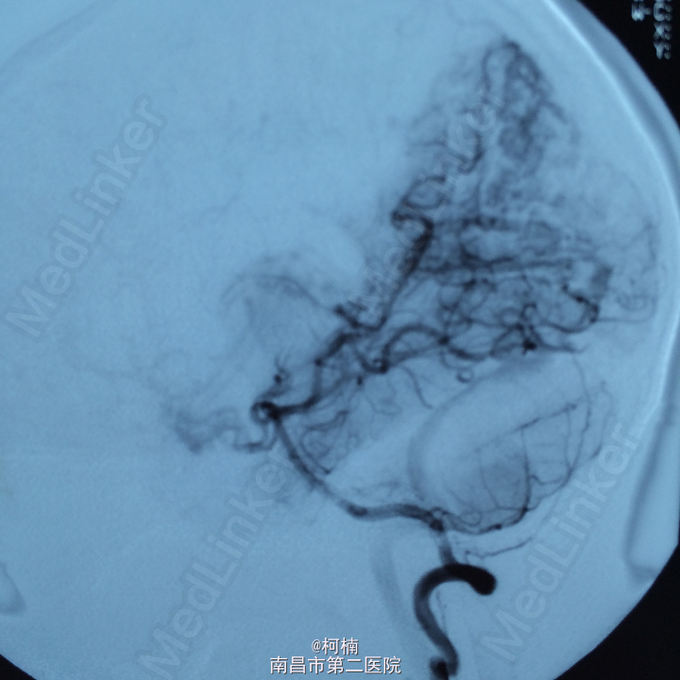

主诉:头痛伴呕吐2天,意识障碍1天 病史:患者于2天前运动后出现头晕头痛,为爆炸样头痛,程度较重,伴呕吐多次,呕吐物均为为内容物,伴四肢乏力,予休息处理。次日清晨患者出现头痛加重,伴呕吐,甚至模糊,呈嗜睡状态,呼之能应,遂急诊送入当地ICU治疗,查头部CT示:蛛网膜下腔出血,予脱水、止血对症治疗后患者症状无明显缓解。转入我院进一步治疗。

查体:神志朦胧,颈抵抗,右侧肢体及躯干深感觉减退,左侧正常。 辅助检查:复查CT提示左侧额叶出血破入脑室系统

诊断:脑动静脉畸形 处理:予急诊行DSA检查,提示脑动静脉畸形,予行血管内栓栓塞治疗